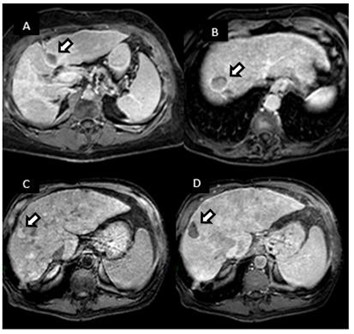

La hiperplasia nodular focal es el segundo tumor benigno más frecuente después del hemangioma. Tiene mayor incidencia en mujeres jóvenes. Histológicamente es un tumor hiperplásico que conserva los mismos componentes del tejido hepático normal, pero con una arquitectura alterada (hepatocitos normales + células de Kupffer + conductos biliares primitivos no conectados con la vía biliar normal). Presentan una cicatriz central de tejido fibroso con estructuras vasculares dilatadas y ectásicas. En la tomografía multicorte sin contraste intravenoso se evidencia como una lesión homogénea bien definida, hipo o isodensa con respecto al parénquima hepático. En la tomografía multicorte multifásica, después de la administración del medio de contraste, tiene un comportamiento típico.

- Fase arterial: reforzamiento intenso.

- Fase portal: es isodenso o ligeramente hiperdenso con respecto al parénquima.

- Fase tardía: lesión totalmente isodensa, no se visualiza, excepto porque puede producir efecto de masa sobre el parénquima adyacente.

La cicatriz central (Anexos 21 y 22), al estar menos vascularizada, no refuerza en fase arterial. Sin embargo, en fase tardía muestra hiperdensidad cuando ya el resto de la lesión se ha hecho isodensa.(18)